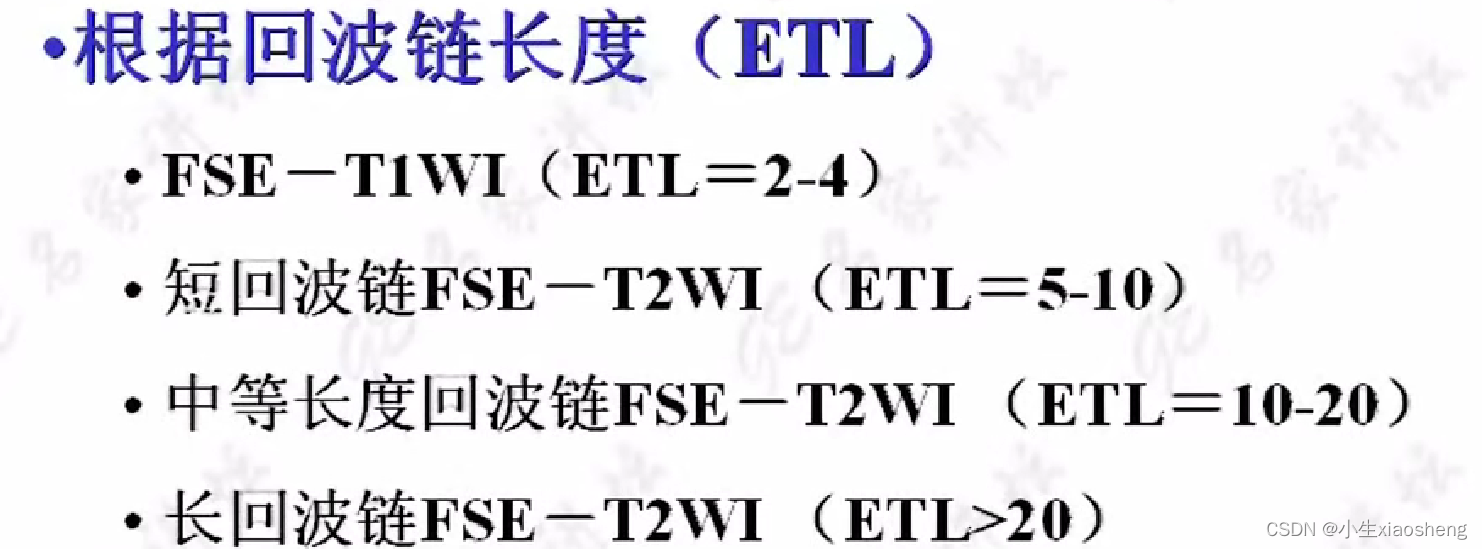

因为这里有很多的180度,所以一次能填充很多K空间线。两个90度之间的时间还是叫做TR,180度的个数叫做ETL,90度到中间个数的180度叫做有效TE,两个180度之间的叫做ES。

根据ETL的长度对FSE进行分类,不想了解这个分类所做的具体事情了😵